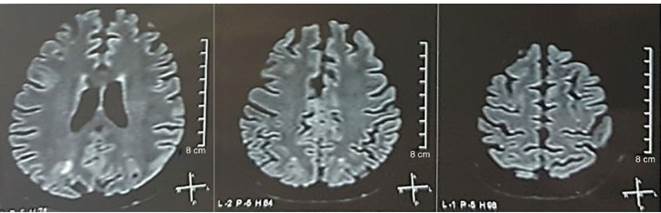

Se solicitó una tomografía de cráneo la cual no mostró signos de isquemia o sangrado; se observó una hipodensidad occipital derecha sin efecto de masa por lo que se amplió la orden de exámenes para filiar su etiología. Se excluyeron causas metabólicas, infecciosas y medicamentosas. Por HTA de difícil control (hasta 190/100 mmHg con tensión arterial media [TAM] de 130 mmHg), requirió hasta 6 antihipertensivos; por sonda nasogástrica con atenolol 50 mg/12 h, losartán 100 mg/día, amlodipino 10 mg/día, doxazosina 2 mg/6 h e intravenosos con nitroprusiato 50 mg/día y furosemida 20 mg/6 h. Por actividad lúpica severa (SLEDAI 21: convulsiones, hematuria, proteinuria, hipocomplementemia, anti-DNA, trombocitopenia), recibió nuevamente tratamiento con metilprednisolona 1 g/3 días. El electroencefalograma no mostró actividad epileptiforme. Se solicitó angiorresonancia cerebral en la cual no se encontraron hallazgos consistentes con vasculitis ni trombosis del sistema nervioso central. En la RMN cerebral se observan imágenes típicas de PRES (fig. 1), cuyo desarrollo estaría con relación al LES exacerbado, HTA severa, glomerulonefritis lúpica y uso de inmunosupresores, por lo que se añadió nimodipino oral 60mg/6h y se controlaron los factores desencadenantes. Por riesgo de lupus inducido por fármacos se retiró gradualmente la fenitoína, con aumento progresivo de levetiracetam hasta 1 g/12 h por sonda nasogástrica. La tabla 1 detalla los estudios complementarios relevantes. Durante el seguimiento no presentó nuevos eventos convulsivos, la función renal se mantuvo estacionaria, mejoraron las cifras tensionales (TAM 85-90 mmHg), disminuyó la actividad lúpica (SLEDAI 13: hematuria, proteinuria, hipocomplementemia, anti-DNA, trombocitopenia). La RMN cerebral de control evidenció involución de las lesiones previas (fig. 2).

Figura 1 Resonancia magnética nuclear de cerebro simple + difusión al ingreso: lesiones bilaterales, simétricas, hiperintensas en secuencia FLAIR en sustancia blanca de lóbulos occipitales y parietales.